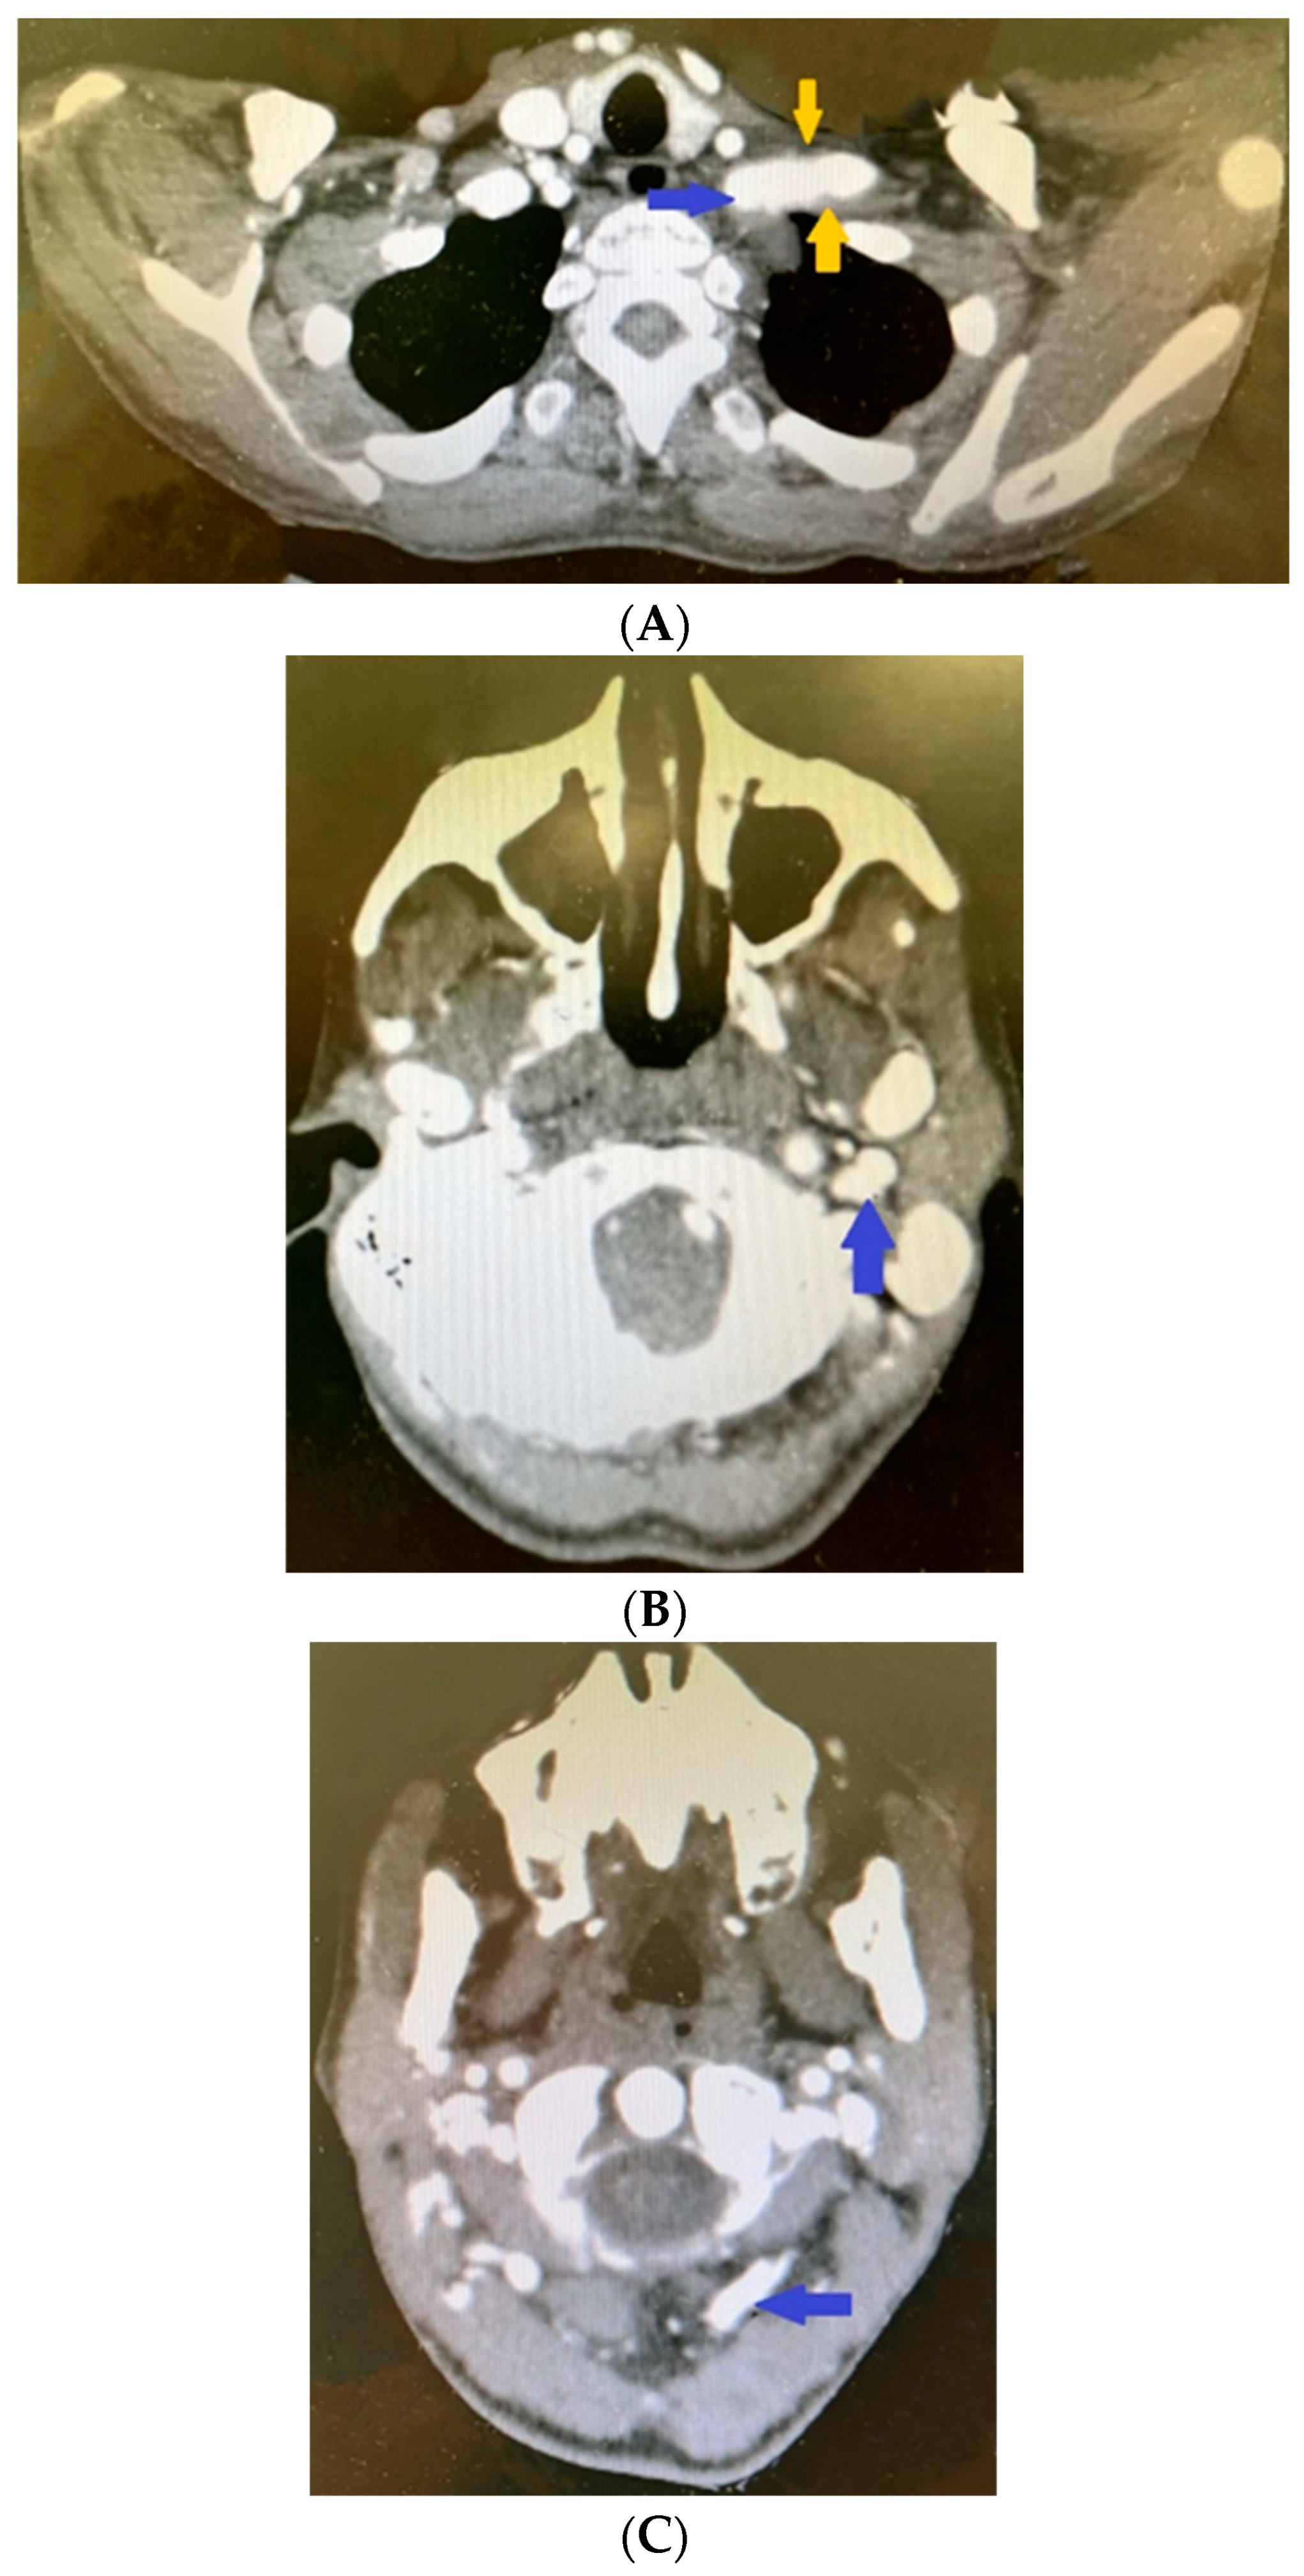

2. Clinical Case Presentation